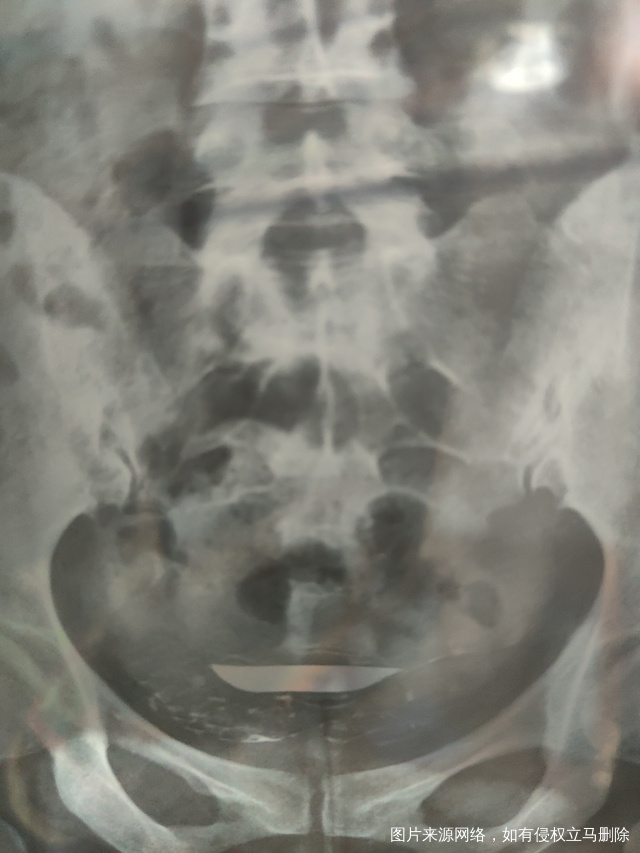

各位医生好前天做了输卵管造影请帮忙看看这些造